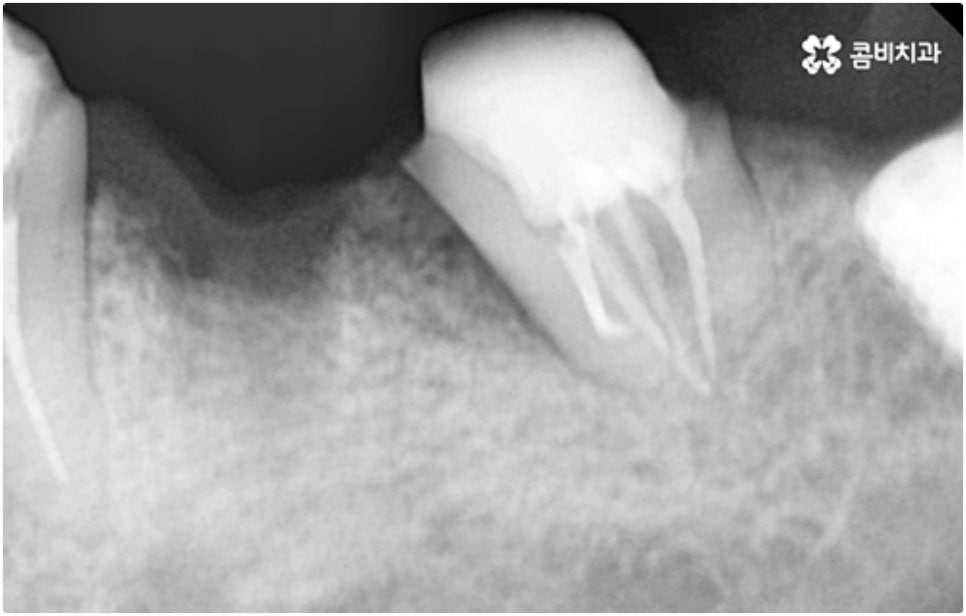

식립 성공률 및 지속적인 안정성을 높이기 위해서는 초기 고정이 잘 이루어져야 하는데 만약에 식립 바탕이 되는 잇몸뼈의 상황이 좋지 않다면 이와 관련된 치료를 먼저 해 줘야 하는 거예요. 예를 들어 치주 질환이 심하다면 이를 깨끗하게 치료해 주는 것이 우선시 되어야 하고, 잇몸뼈의 높이나 밀도 등이 부족한 경우에는 뼈이식 과정을 통해 이를 먼저 보충해 줄 필요가 있어요. 또한 윗어금니가 빠진지 오랜 시간이 지나 이미 골흡수가 일어나고 상악동이 많이 내려와 있다면 상악동 거상술 및 뼈이식을 한 후 임플란트 식립을 진행해야 할 거예요.

이와 같이 상악의 경우 상악동과 비강저(콧구멍 바닥)까지의 거리 및 신경과 혈관분포, 하악의 경우 하치조 신경 및 하치조관과 이공까지의 거리, 주위 조직 등에 대한 면밀한 검진과 파악이 필요하기 때문에 임플란트 시술을 진행할 때 상하악골 및 주변 조직을 해부학적으로 자세히 체크할 수 있는 정밀 장비 및 담당 의료진의 숙련도가 굉장히 중요한 요소라고 할 수 있어요.

어금니는 저작력이 많이 걸리는 치아이기 때문에 보철물 제작에 있어서도 강한 자극에 잘 견딜 수 있는 튼튼한 재질을 고르는 것이 중요한데 요즘은 이러한 내구성과 함께 심미적인 부분도 함께 고려하는 추세라서 어금니임플란트 시술시 지르코니아 크라운을 선택하시는 분들이 많이 있습니다.